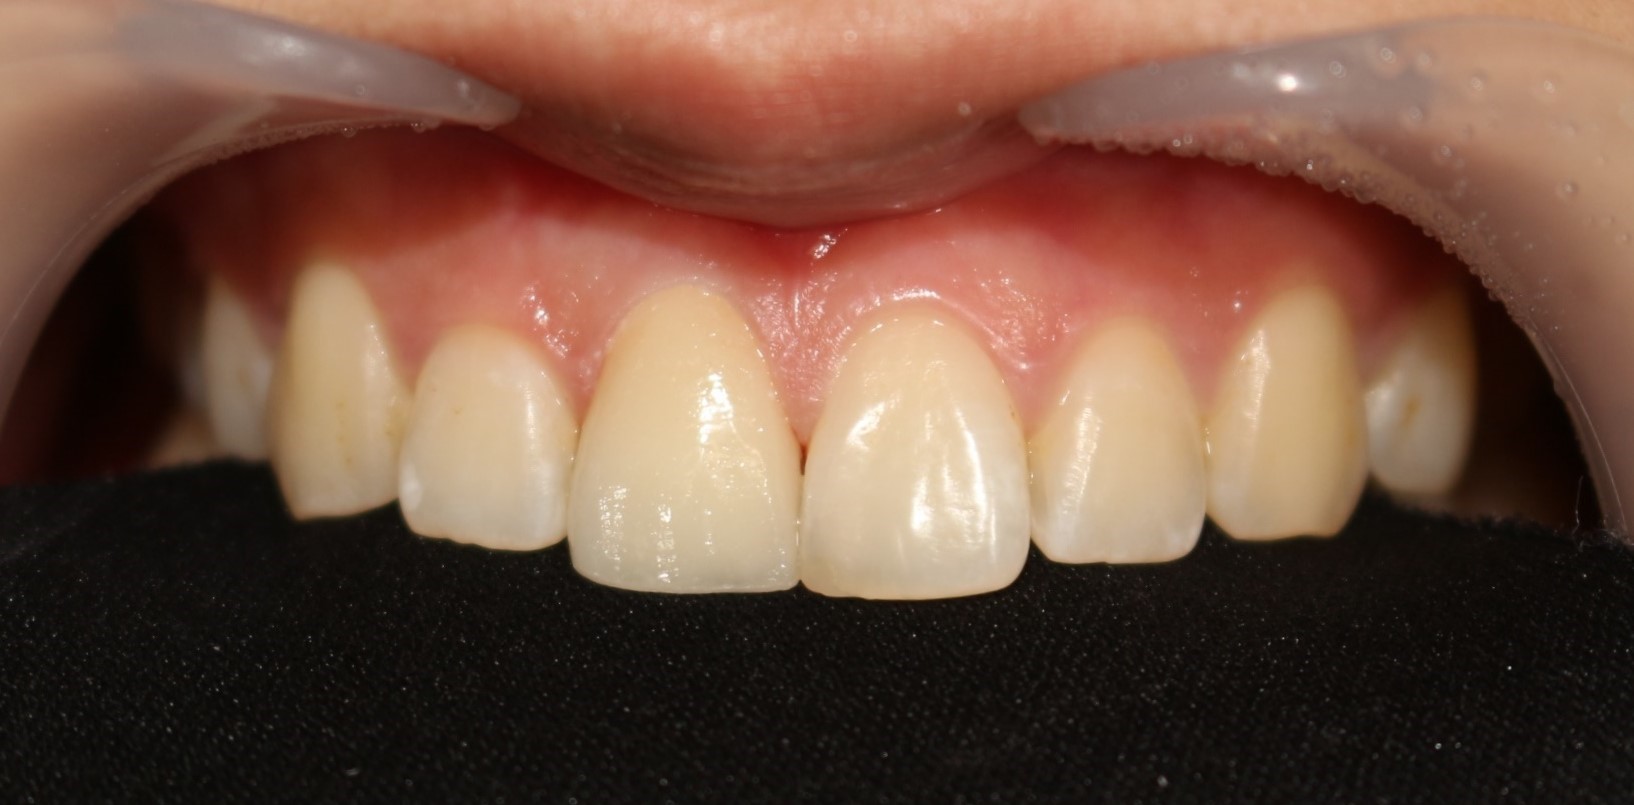

수술 전

수술 후

전치부 치아 파절 크라운치료 (PFZ)

전후사진